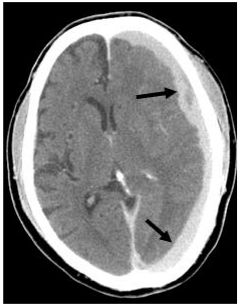

29.頭部外傷的病人,CT影像如下圖,箭號所指的是: (A)硬腦膜上血腫(epidural hematoma,EDH) (B)硬腦膜下血腫(subdural hematoma,SDH) (C)硬腦膜下積水(subdural effusion,SDE) (D)挫傷性腦內出血(contusion intracerebral hemorrhage)